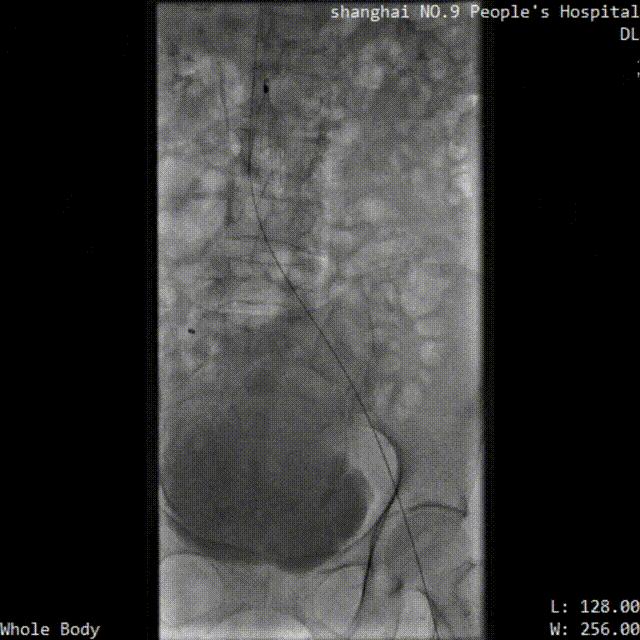

※ LuVoCaptor取栓前后管腔造影对照:

取栓术前管腔造影

取栓术后管腔造影

※ 手术过程:

患者仰卧位,穿刺膝右侧股总静脉,造影定位下腔静脉,肾静脉位置,放置可回收腔静脉滤器;穿刺左侧腘静脉,置入导鞘,使用LuVoCaptor取栓导管作用靶病变,实施取栓后,即刻造影检查示血栓清除率>90%。导丝导管配合通过左髂静脉狭窄闭塞段返回真腔,后行球囊扩张术,再植入Wallstent支架。再次造影见左股浅静脉、股静脉、髂静脉、腔静脉、滤器内连续显影,未见明显充盈缺损,管壁形态血流速度快,造影剂无外渗。